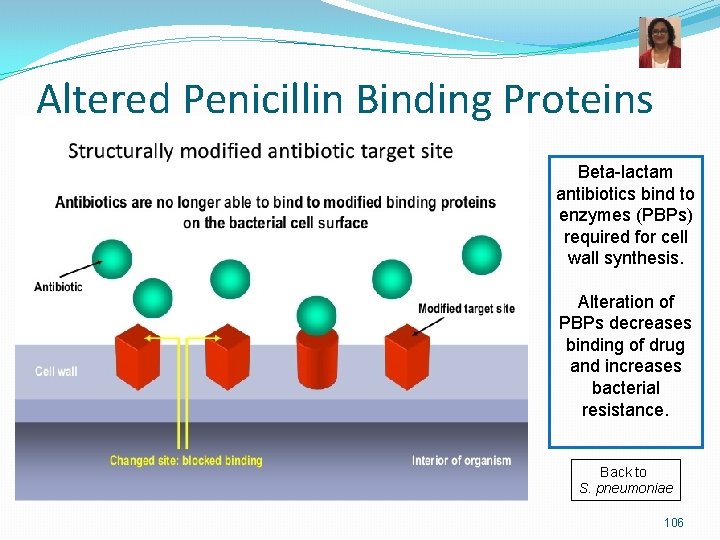

Pneumococcal Infections Treatment n Treatment: n n Beta-lactams = penicillin or 3 rd generation cephalosporin, clindamycin, vancomycin Resistance to penicillin is now common altered penicillin-binding proteins - all S. pneumoniae isolates should be tested for susceptibility to beta-lactams Pneumococcal Infections Prevention n PPSV: pneumococcal polysaccharide vaccine = 23 -valent polysaccharide vaccine n PCV: pneumococcal conjugate vaccine = 13 -valent conjugated vaccine for children < 60 months 23

Altered Penicillin Binding Proteins Beta-lactam antibiotics bind to enzymes (PBPs) required for cell wall synthesis. Alteration of PBPs decreases binding of drug and increases bacterial resistance. Back to S. pneumoniae 106